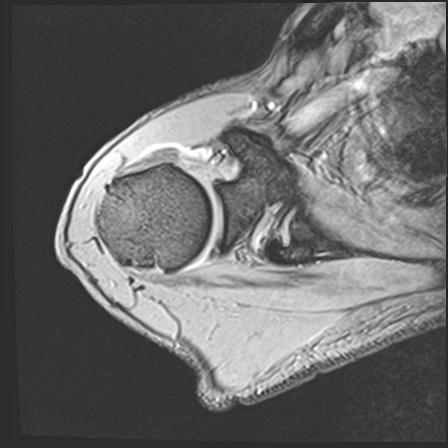

110214 12/20 肩 2R 12/21 肩 4R 72歳女性 左上腕外科頚プレート